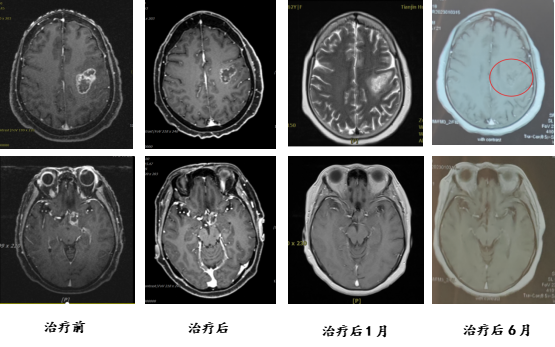

Patient Qu, a 61-year-old female, presented with progressive speech difficulties three months prior to admission. PET-CT revealed multiple irregularly shaped MET and FDG hypermetabolic lesions in the left frontal cortex, subcortical left frontal lobe adjacent to the left ventricle, the left optic tract region of the suprasellar cistern, and the sellar region. A biopsy confirmed the diagnosis of glioblastoma, WHO grade IV. She was admitted for carbon ion therapy. Upon admission, the patient exhibited speech difficulties, with largely intact comprehension, judgment, calculation, and memory, but slightly impaired orientation. Following treatment, her speech difficulties and orientation showed improvement.

Efficacy comparison: